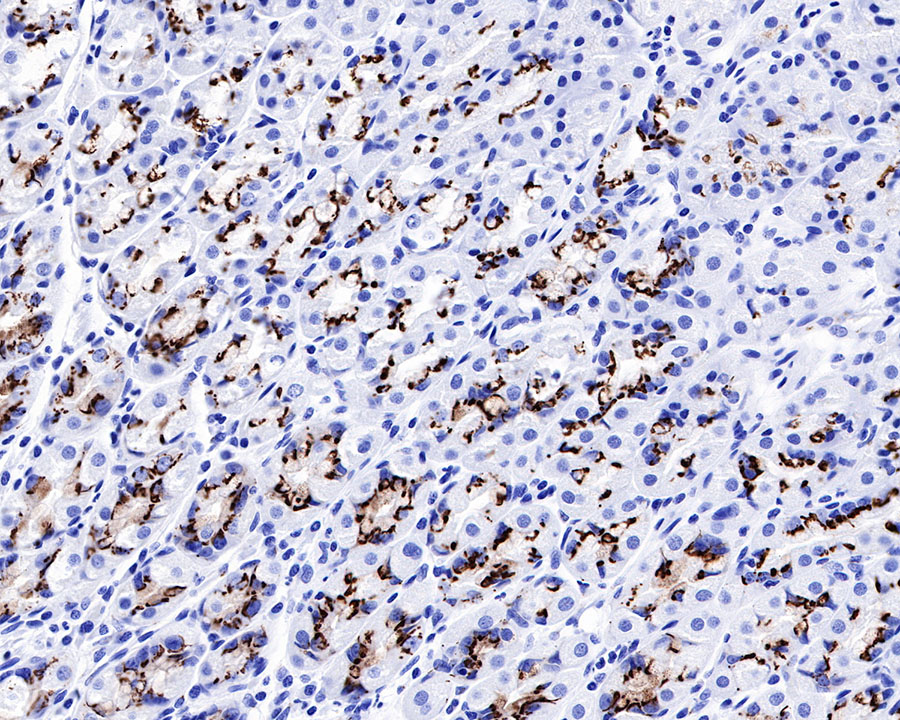

IHC shows positive staining in paraffin-embedded human stomach. Anti-GP73/GOLPH2 antibody was used at 1/1000 dilution, followed by a HRP Polymer for Mouse & Rabbit IgG (ready to use). Counterstained with hematoxylin. Heat mediated antigen retrieval with Tris/EDTA buffer pH9.0 was performed before commencing with IHC staining protocol.